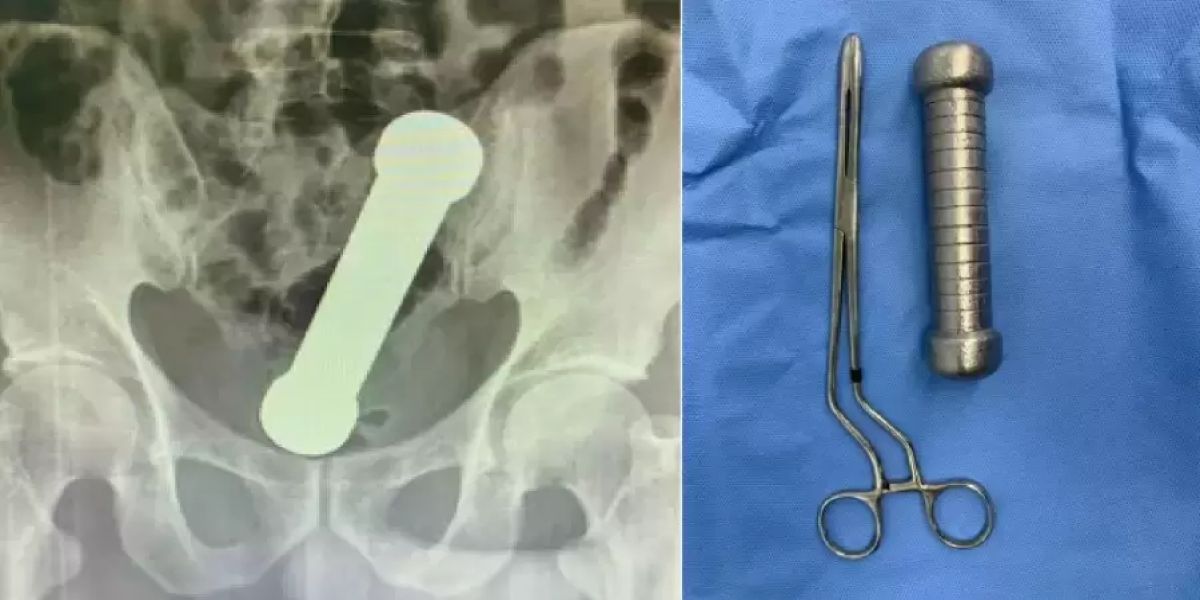

Um homem de 54 anos ficou com um haltere de cerca de 2 kg preso no reto e precisou ser socorrido em um hospital em Manaus. O caso acabou virando um artigo científico e foi publicado no início deste mês na revista científica International Journal of Surgery Case Reports.

Segundo o estudo, o homem, cuja identidade não foi revelada, chegou ao hospital com queixa de dor abdominal, náuseas, vômitos e dificuldade de evacuação. Os médicos decidiram pedir exames de radiografia da região abdominal e foram surpreendidos com a presença "de um corpo estranho em forma de haltere de exercício", diz o artigo. Não havia sinais de perfuração no corpo dele.

O paciente foi encaminhado ao centro cirúrgico, para a retirada do objeto, que ocorreu sem o auxílio de instrumentos.